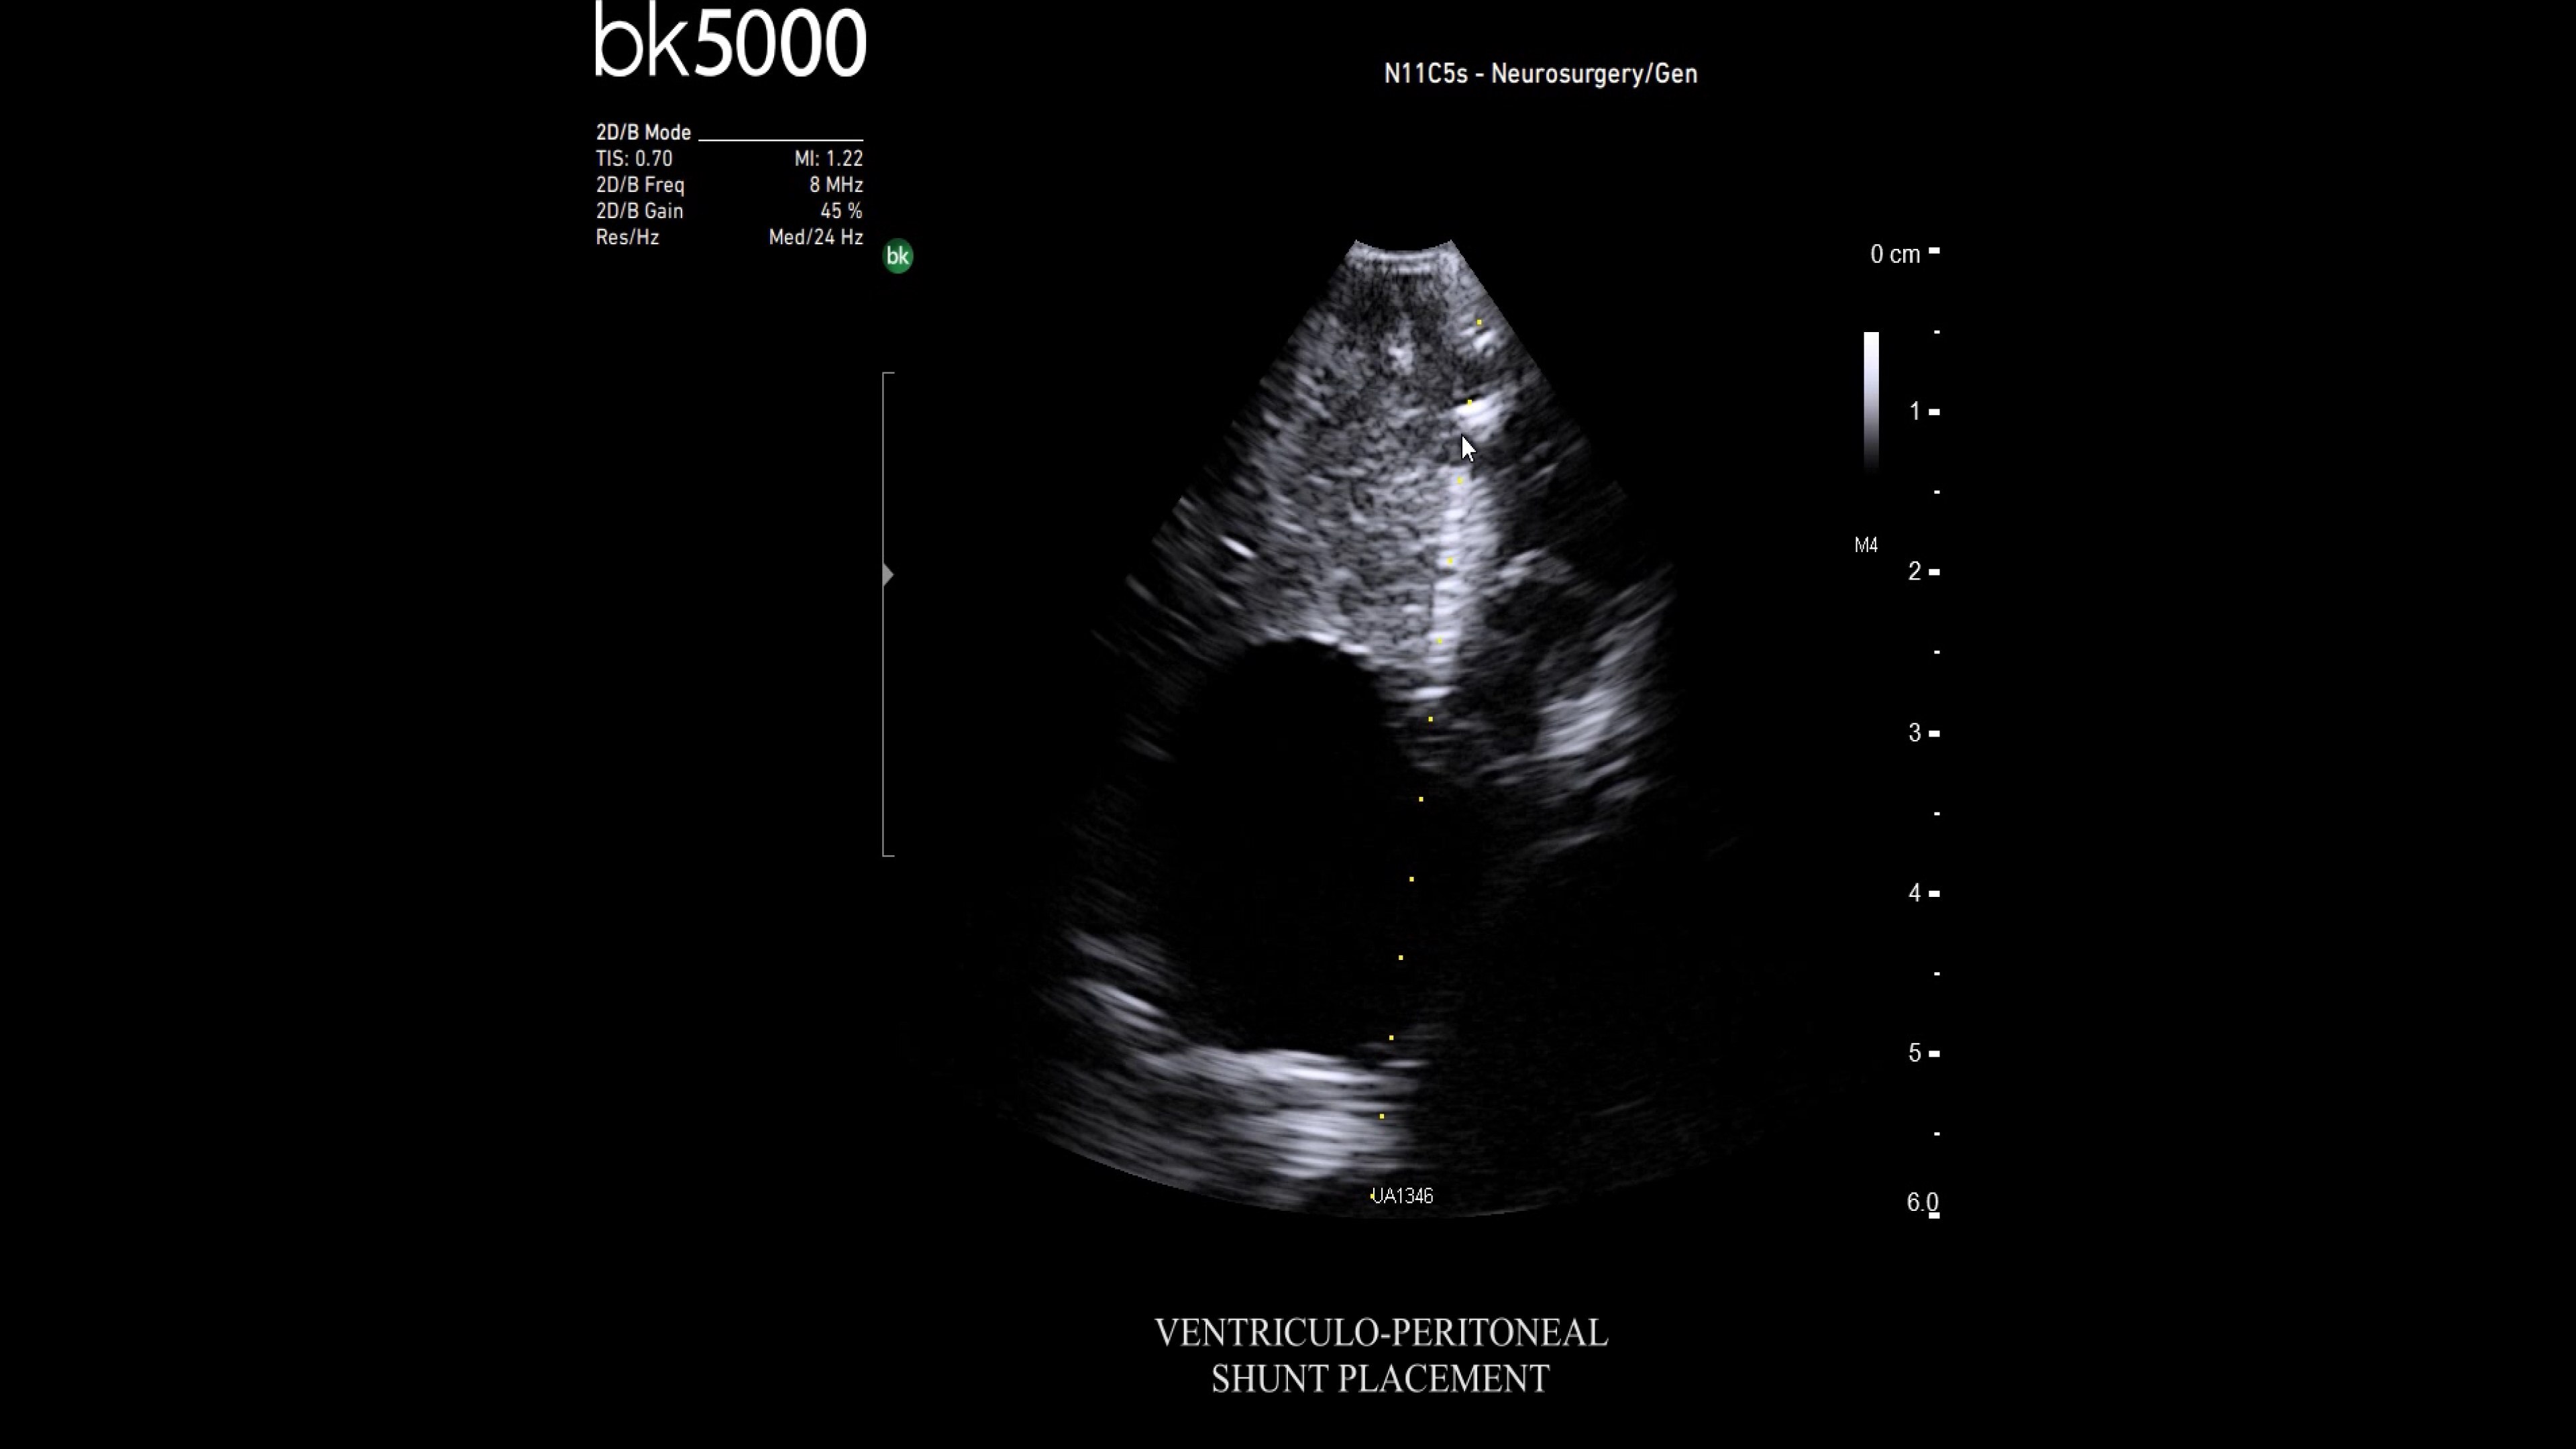

Neurosurgery

Premium ultrasound imaging in neurosurgical procedures

Ultrasound enhances neurosurgery by providing real-time navigation and lesion identification, crucial as preoperative CT/MRI data can be outdated. The bk5000 system offers high-quality images to see lesion margins and determine actions. Advanced graphics processing ensures immediate, auto-optimized images.

• Neurosurgery transducers: High-resolution, sterilizable transducers provide detailed brain and spinal cord images. The Smart™ button allows easy activation, freezing, storing, or printing of images. Disposable needle guides aid lesion targeting.